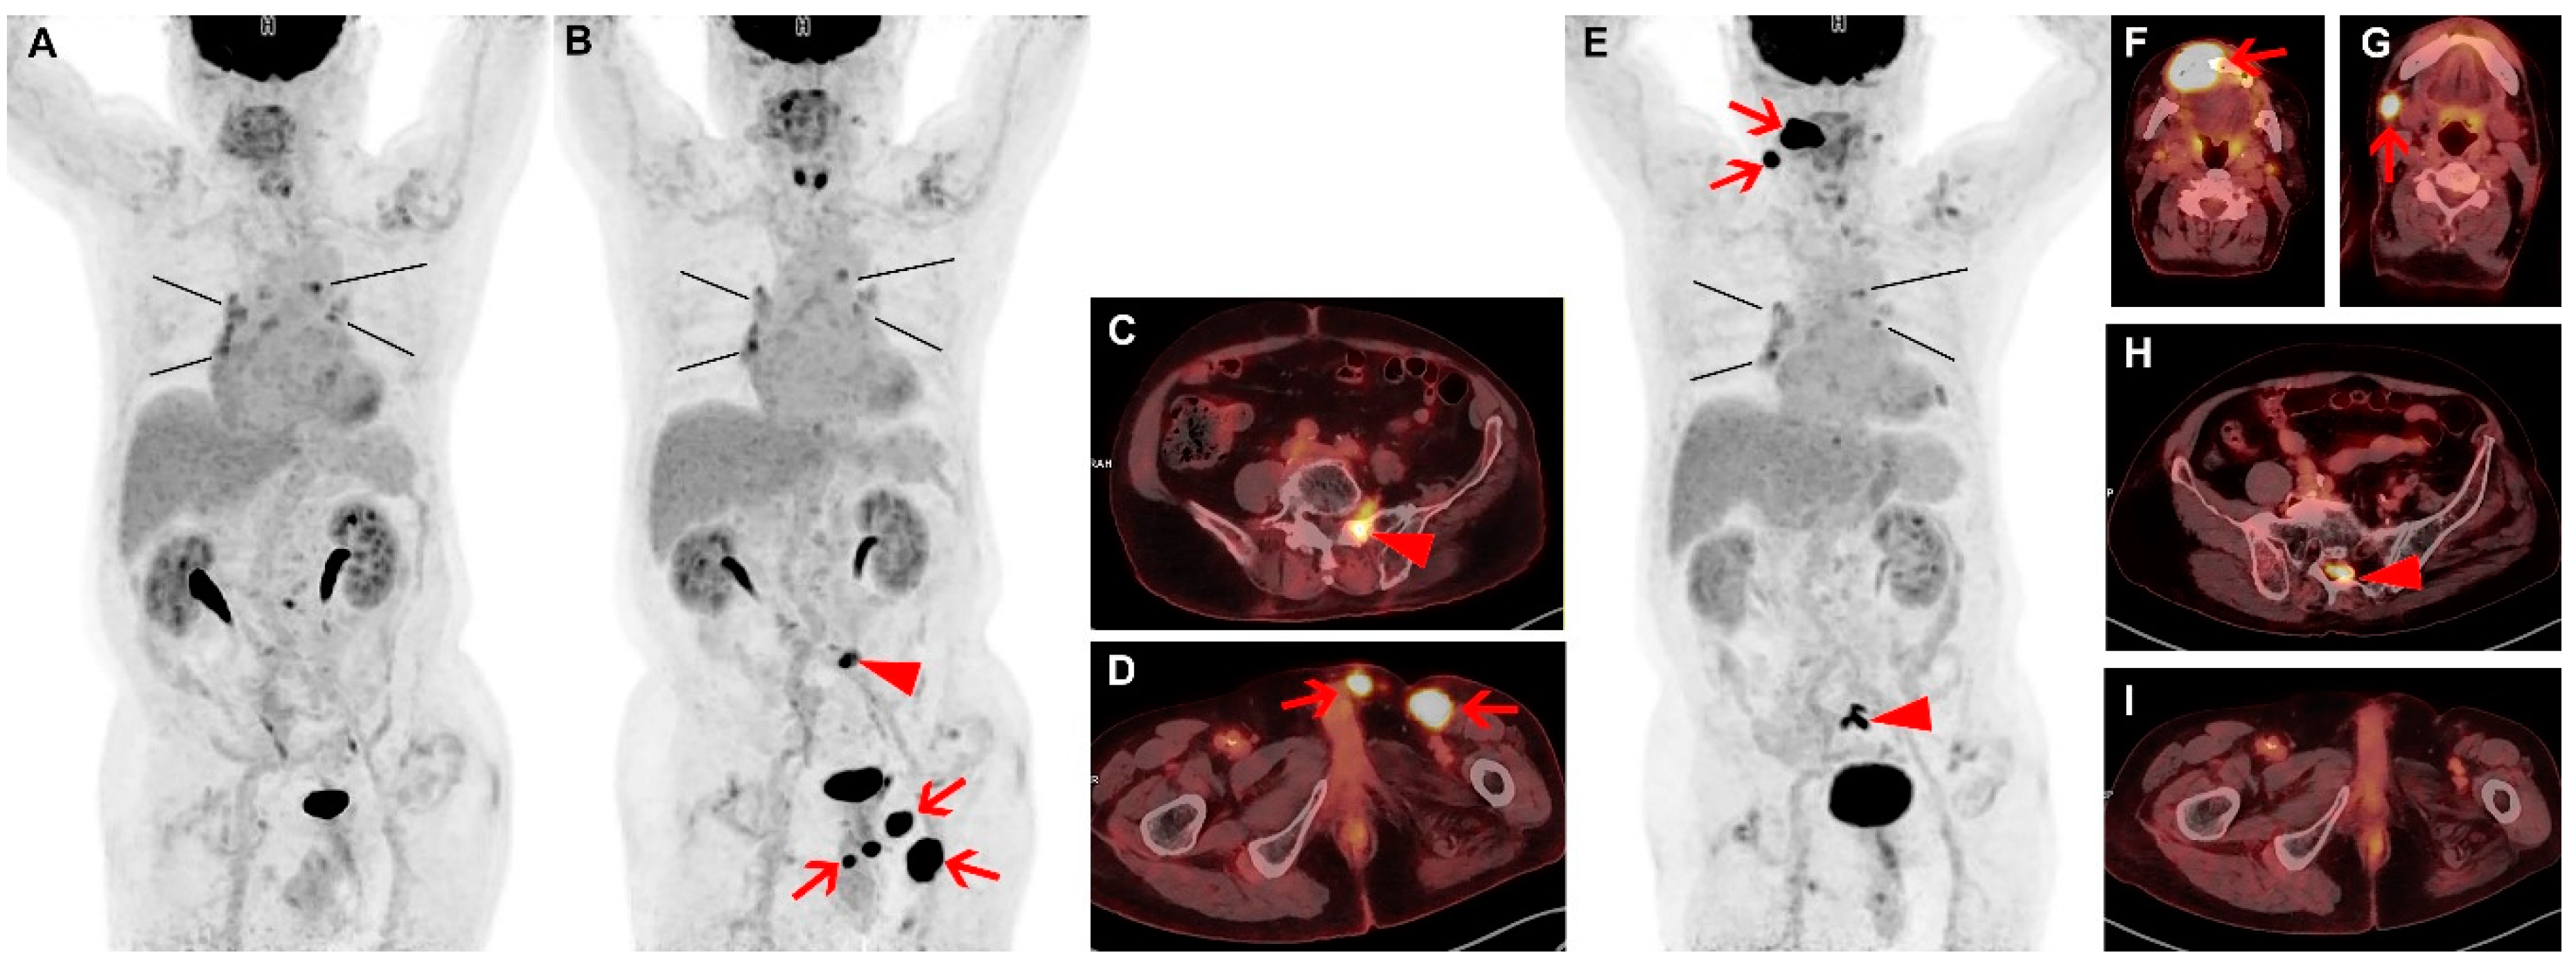

Spontaneous Remission and Concomitant Progression in a Patient with DLBCL